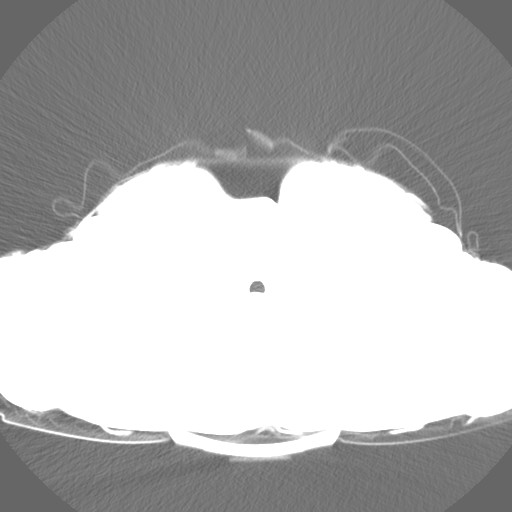

Bu da çekilen BT sanırım, gördükleriniz neyi ifade ediyor? Yanlış görüntüleri attıysam kusura bakmayın internetteki gibi akciğerin düz göründüğünü gördüğüm fotoğraf yoktu. Gerçekten 1 yıldan fazla süren geçmeyen öksürük, üst solunum yolu enfeksiyonu denilen bir hastalık varsa ve bu 3 haftada geçebiliyorsa, nasıl oluyor da hastalığı bu olabilir?

Bu da başka bir değer sanırım ama gözüküyor mu lekeler bilmiyorum, fotoğraf indirirken de böyle küçük ve kalitesiz geldi biraz.

Bu da lekelerin gözüktüğü, tam olarak anlamadım ve e-Devlet'te de aynı bu vardı başta. Bir sürü resim var, acaba size ZIP olarak hepsini göndersem baksanız? Çünkü internetteki gibi BT değil, farklı bir çekim mi acaba bu, belki de başka bir organdır? Özel bilgiler var mıdır ZIP'in içerisinde hepsini atmam problem olur mu? Baktığım fotoğraflar genellikle hep aynı, seri değişince değişiyor. Bazıları Full beyaz görüntü. İlk defa baktığım için yanlış bir şey attıysam kusura bakmayın. Bu fotoğrafları e-Devlet'in radyolojik yerinden aldım, e postaya yolladım.

Bu da çekilen BT sanırım, gördükleriniz neyi ifade ediyor? Yanlış görüntüleri attıysam kusura bakmayın internetteki gibi akciğerin düz göründüğünü gördüğüm fotoğraf yoktu. Gerçekten 1 yıldan fazla süren geçmeyen öksürük, üst solunum yolu enfeksiyonu denilen bir hastalık varsa ve bu 3 haftada geçebiliyorsa, nasıl oluyor da hastalığı bu olabilir?

Bu da başka bir değer sanırım ama gözüküyor mu lekeler bilmiyorum, fotoğraf indirirken de böyle küçük ve kalitesiz geldi biraz.

Bu da lekelerin gözüktüğü, tam olarak anlamadım ve e-Devlet'te de aynı bu vardı başta. Bir sürü resim var, acaba size ZIP olarak hepsini göndersem baksanız? Çünkü internetteki gibi BT değil, farklı bir çekim mi acaba bu, belki de başka bir organdır? Özel bilgiler var mıdır ZIP'in içerisinde hepsini atmam problem olur mu? Baktığım fotoğraflar genellikle hep aynı, seri değişince değişiyor. Bazıları Full beyaz görüntü. İlk defa baktığım için yanlış bir şey attıysam kusura bakmayın. Bu fotoğrafları e-Devlet'in radyolojik yerinden aldım, e postaya yolladım.